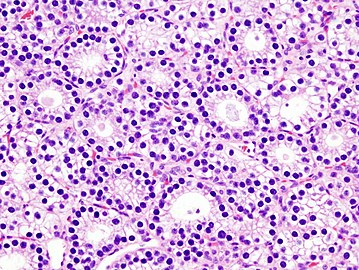

Parathyroid Adenoma

A parathyroid adenoma is a benign tumor of the parathyroid gland. It generally causes hyperparathyroidism; there are very few reports of parathyroid adenomas that were not associated with hyperparathyroidism.[1]

There are typically four parathyroid glands located on the posterior surface of the thyroid. In order to maintain calcium metabolism, the parathyroid glands secrete parathyroid hormone (PTH) which stimulates the bones to release calcium and the kidneys to reabsorb it from the urine into the blood, thereby increasing its serum level. The action of calcitonin opposes PTH. When a parathyroid adenoma causes hyperparathyroidism, more parathyroid hormone is secreted, causing the calcium concentration of the blood to rise, resulting in hypercalcemia.[2]